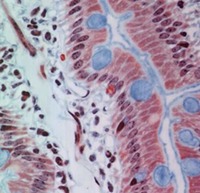

Stratified Columnar epithelium is rare. One place you can find it is in the largest ducts of salivary glands (parotid, submandibular, etc). The basal layer of cells are cuboidal cells and the layer nearest the apical surface includes columnar cells. The large droplets are mucus, in Goblet cells. This also illustrates the fact that epithelia are classified according to the cells nearest the lumen, in this case columnar.

Below is another view of a large (excretory) duct of a salivary gland showing the mucin in Goblet cells after a special stain. What might be the advantages of an epithelium that has a basal cuboidal cell layer and an apical columnar cell layer?